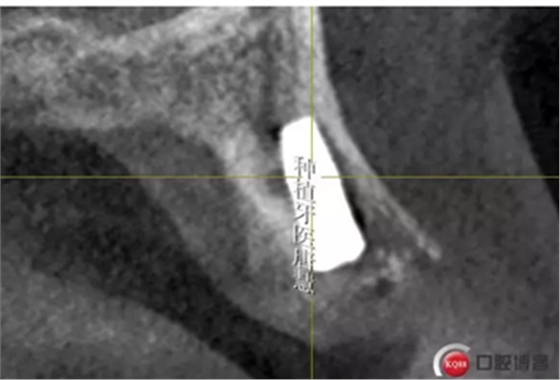

頰側(cè)骨皮質(zhì)缺失